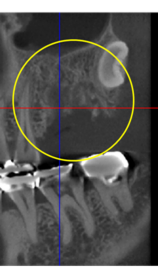

抜歯のう胞摘出

Perio Wave+Er:YAGレーザー+コールドレーザーで治療した箇所の経過です。

左から直後、1ヶ月経過時、2ヶ月経過時の画像です。

骨再生の確認をした際の動画です。

画像をクリックすると、youtubeにジャンプします。